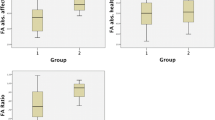

Stimulation at 100% of MSO of right motor cortex was not able to evoke MEPs from left and right FDI muscles even at intensity of 100% MSO at rest and during MVC. On the other hand, after single pulse at 100% MSO of left motor cortex, MEPs were recorded on both FDI. After, a single-pulse TMS on left motor cortex MEPs elicited and recorded from both FDI muscles had a similar latency (cMEPs: 20.5 vs. iMEPs: 21.2 ms). Neurophysiological results are shown in Fig. 4.

Histograms show pre- and post-surgical neurophysiological examination by single and paired TMS of left motor cortex and recordings from both sides. Contralateral SICI (cSICI) and ipsilateral ICF (iICF) were increased after surgery. Both contra- and ipsilateral Cortical Silent Periods (cCSP and iCSP) were reduced after surgery. *p < 0.05, level of significance

Presurgical TMS evaluation showed no response after affected hemisphere stimulation but showed bilateral activation after left hemisphere stimulation and because MR-tractography disclosed interruption of CSP on right hemisphere, preoperative work-up indicated the left motor cortex as the functioning cortex with bilateral representation. Moreover, neurophysiological evaluation before and after surgery revealed modification of intracortical connections. In particular, motor threshold and MEP latencies were unchanged while contralateral SICI and ipsilateral ICF were increased after hemispherectomy. After surgery, patient showed a better control of seizures. Because the level of SICI is related to the level of intracortical GABAA activity [28], its increase after surgery might explain the effects on seizure control. On the other hand, ICF origin is more complex and probably it may be influenced by multiple neurotransmitters systems [22]. Before surgery, patient showed an asymmetric hand motor impairment (right > left) and after surgery motor performances did not worsen but, interestingly, manual dexterity improved and this long-lasting effect may be explained by a plastic change of motor cortex [29]. It is conceivable that damaged hemisphere might exert a negative effect on the functional hemisphere. Early brain lesion causing maladaptive interhemispheric interaction due to interhemispheric rivalry and interhemispheric imbalance [30] may explain this effect. It is confirmed by positive effects of functional hemispherectomy on motor performances, and it is in accordance with previous studies involving non-invasive brain stimulation techniques [16]. Besides, improvements after functional hemispherectomy may suggest that stopping interhemispheric imbalance may be beneficial both on seizures control and motor control. Moreover, TMS evaluation demonstrated enhancement of cSICI and iICF that are effects of intracortical excitatory and inhibitory phenomena [22, 28], and these long-lasting effects, recorded 6 months after surgery, may be due to intracortical plasticity phenomena induced by functional hemispherectomy [13]. Several studies demonstrated that integrity of CST is crucial for motor recovery [31, 32]. In our patient, DTI analysis and 3D fiber-tracking demonstrated extensive loss of the right CST trajectories and FA reduction across the remaining pathways suggesting severe CST structural damage; this finding may explain the unresponsiveness of LFDI to right motor cortex stimulation by TMS. Moreover, several studies tried to find reliable prognostic biomarkers [31, 32], but conclusive results are lacking.